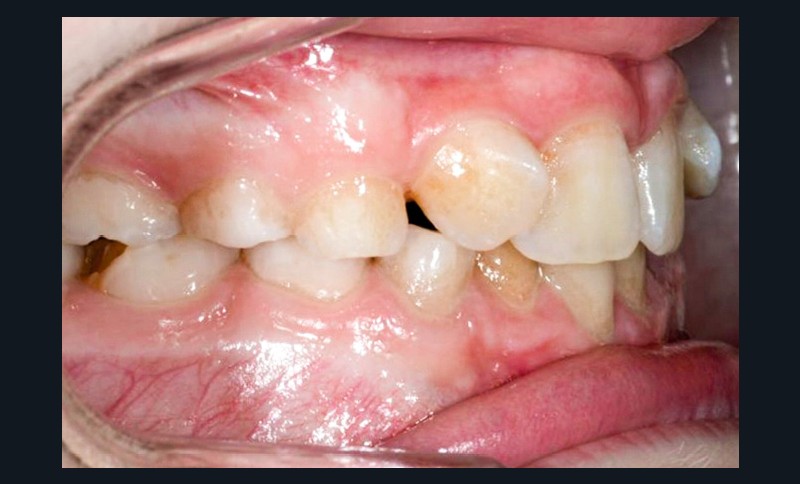

La patiente consulte à l’âge de 9 ans pour la malposition de ses incisives latérales maxillaires. Elle présente une occlusion de Classe I bilatérale sur un schéma normodivergent avec une dysharmonie dento-maxillaire en denture mixte. À l’arcade maxillaire, elle présente une endoalvéolie avec rotations mésiopalatines de 16 et 26.

Sur la radiographie panoramique, on observe une transposition des canines maxillaires en place d’incisives latérales, au contact des racines de 11 et 21.